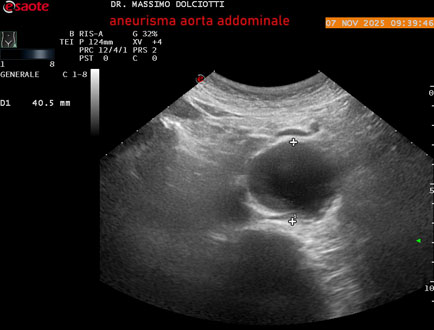

Data inserimento: 11/11/2025

Ecografia del: 07/11/2025

Strumento: Esaote MyLab Eight

Sonda: Convex Multifrequenza 1-8 MHz

Età Paziente: M 60 anni

Motivazione dell'esame: follow up per aneurisma dell'aorta addominale.

Commento all'esame: le immagini ed il video documentano la presenza dell'aneurisma dell'aorta addominale sotto-renale, con diametro antero-posteriore massimo documentato di 47 / 48 mm.

Conclusioni: aneurisma dell'aorta addominale in follow up (abdominal aortic aneurysm follow-up).

Presentazione: Dr. Massimo Dolciotti - Ancona

Elaborazione digitale: Andrea Dini - Ancona